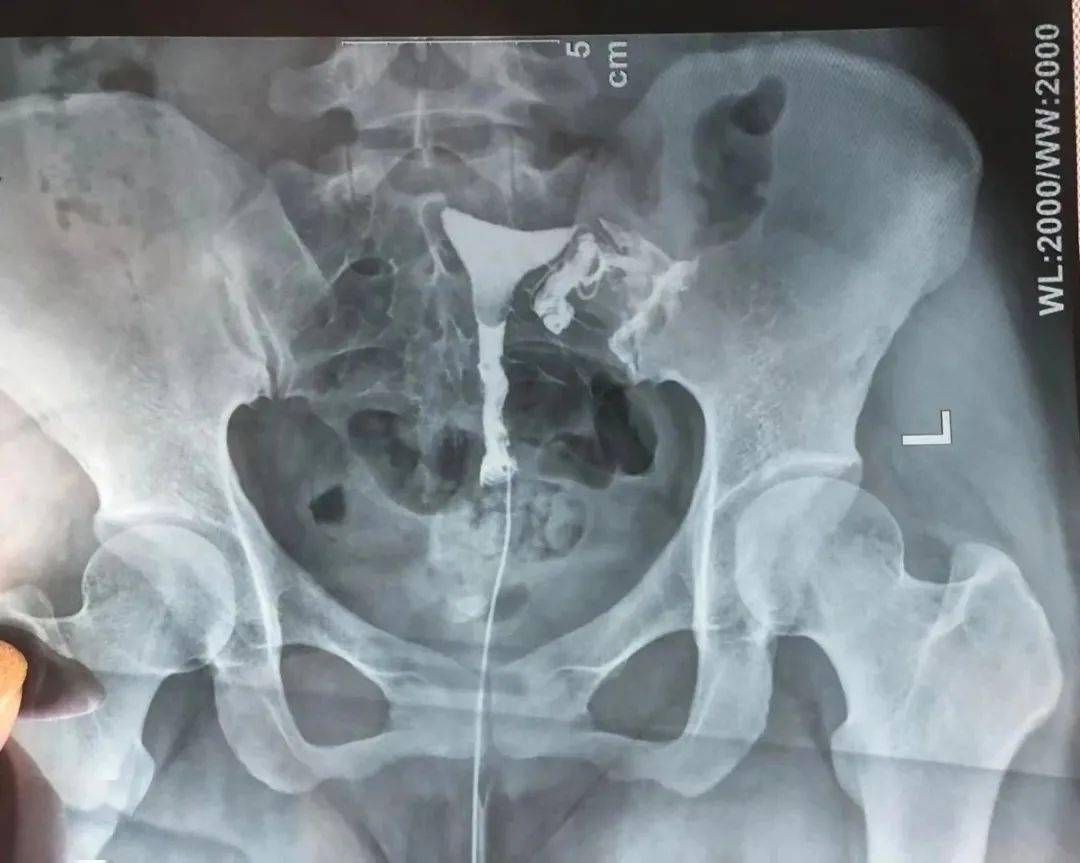

子宫输卵管造影检查的临床应用

图片尺寸960x720